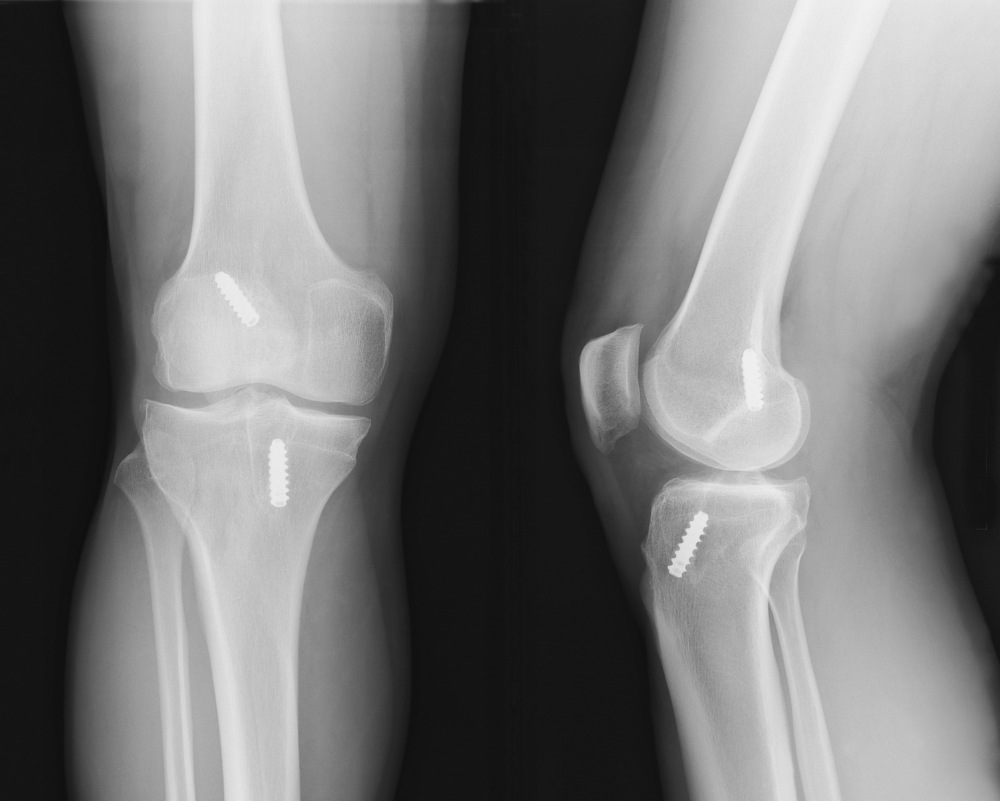

Leg Fractures

Fractures of your tibia, fibula, or patella are serious injuries that require special care.

Dr. Mehta uses advanced surgical and rehabilitation methods to help you recover your active life with confidence.

ACL Tear

Did you hear a popping sound, and now your knee feels painful and unstable? It could be an ACL tear.

Dr. Mehta can guide you on the best treatment to help you heal and regain stability.